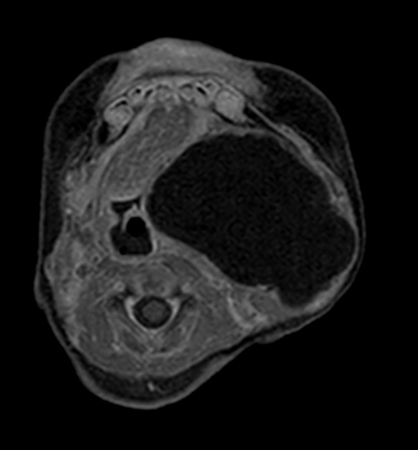

Axial mDIXON XD - T2w TSE (Water only)

Axial mDIXON XD - T2w TSE (In Phase)